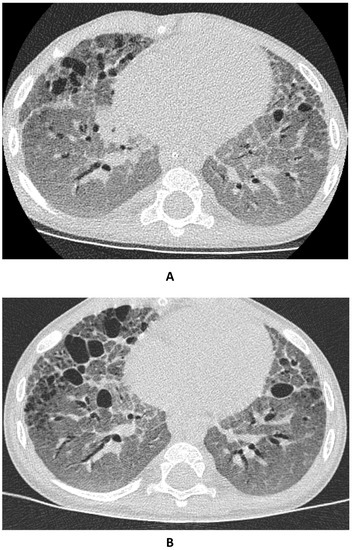

3.2. Respiratory Condition

- Mechri, M.; Epaud, R.; Emond, S.; Coulomb, A.; Jaubert, F.; Tarrant, A.; Feldmann, D.; Flamein, F.; Clement, A.; de Blic, J.; et al. Surfactant protein C gene (SFTPC) mutation-associated lung disease: High-resolution computed tomography (HRCT) findings and its relation to histological analysis. Pediatr. Pulmonol. 2010, 45, 1021–1029. [Google Scholar] [CrossRef] [PubMed]